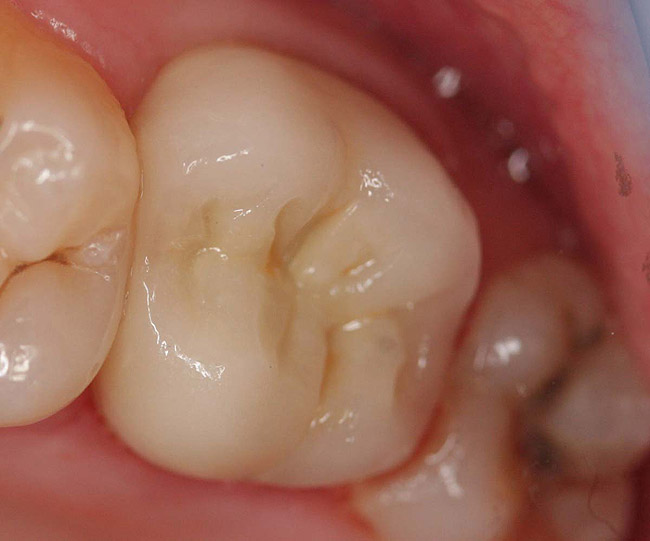

Figure 6  Endodontically treated maxillary right second molar.

Figure 6